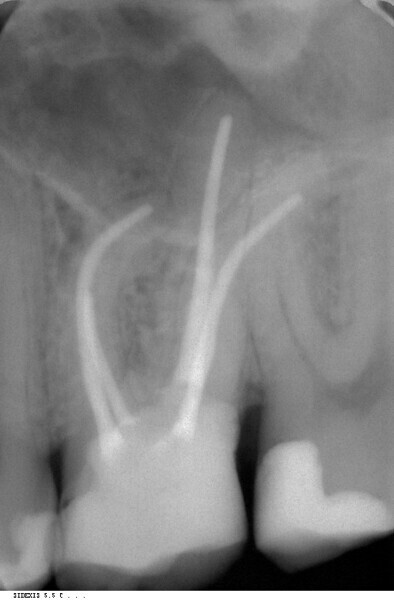

Endodontic follow-up in strongly curved root canals